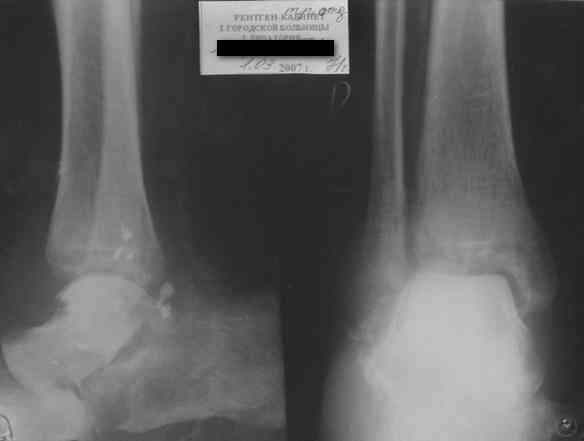

Последний снимок

Мнение по поводу тарана? АН есть?

Операцию планируем на пятницу. План заведующего - двухсуставной артродез АВФ. Скину если получится фото и послеоперационные Р-граммы.

> Мнение по поводу тарана? АН есть?

Типичная картина некроза.

> Операцию планируем на пятницу. План заведующего - двухсуставной

> артродез АВФ. Скину если получится фото и послеоперационные Р-граммы.

Если очаг инфекции - не весь блок, и удастся инфицированную часть хорошо убрать, то будут неплохие шансы на васкуляризацю тарана с двух сторон. Послеоперационные рентгенограммы, конечно, будет интересно посмотреть. Они, правда, вряд ли прогноз надежно отразят.

На мой взгляд, у больного асептический некроз таранной кости, осложненный гнойным артритом голеностопного сустава (по снимку не понятно, что это - фистулография или простая рентгенограмма). Оптимален артродез голеностопного сустава, объем резекции таранной кости определится только интраоперационно. Большая проблема - метод фиксации. Работая, в основном, с пациентами пожилого и старческого возраста могу сказать, что ЧКОС они переносят плохо. Адекватный уход за аппаратом возможен только в условиях стационара. Возможность самостоятельной работы с аппаратом, например для ликвидации укорочения, крайне сомнительна. Кроме того, укорочение 3 см (до 5 см) у данной категории больных легче компенсировать ортопедической обувью. К сожалению и фиксирующие повязки (гипсовые и различные "касты")- не лучший вариант для пожилых людей (пролежни и флектены просто на "ровном месте"). В данном случае я бы применил простую "фиксирующею" компоновку аппарата Илизарова, с возможностью "отступления" к голеностопному брэйсу (тутору). Основная задача - максимальное восстановление самообслуживания больного и, по возможности, избежать "этапных" операций.

-у больного асептический некроз таранной кости,

осложненный гнойным артритом голеностопного сустава (по снимку не понятно, что это - фистулография или простая рентгенограмма-

Ну гнойный артрит вряд ли, свищ-то есть, а всего остального (признаков артрита) нет. А снимок - обычная Р-грамма с артефактами.